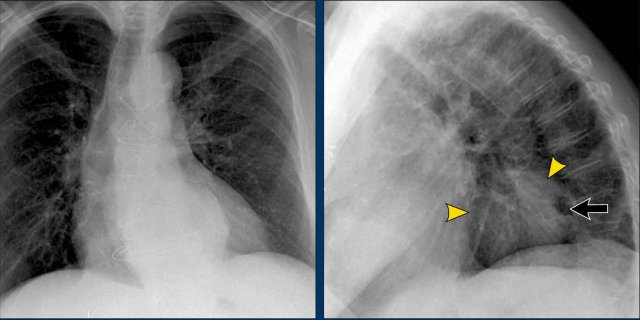

Displacement of the Azygoesophageal Line (1) – Hiatal hernia

A hiatal hernia (arrowheads) is the most common cause of displacement of the azygoesophageal line as seen on the PA-view.

Notice the air within the hernia on the lateral view (black arrow).